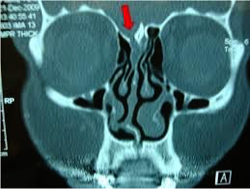

Due to injury of the roof of the nose and the dura

Unilateral watery rhinorrhea increases by bending forward, exertion, and coughing

- Diagnosis is confirmed by biochemical analysis (Beta-2-transferrin) and by radiology